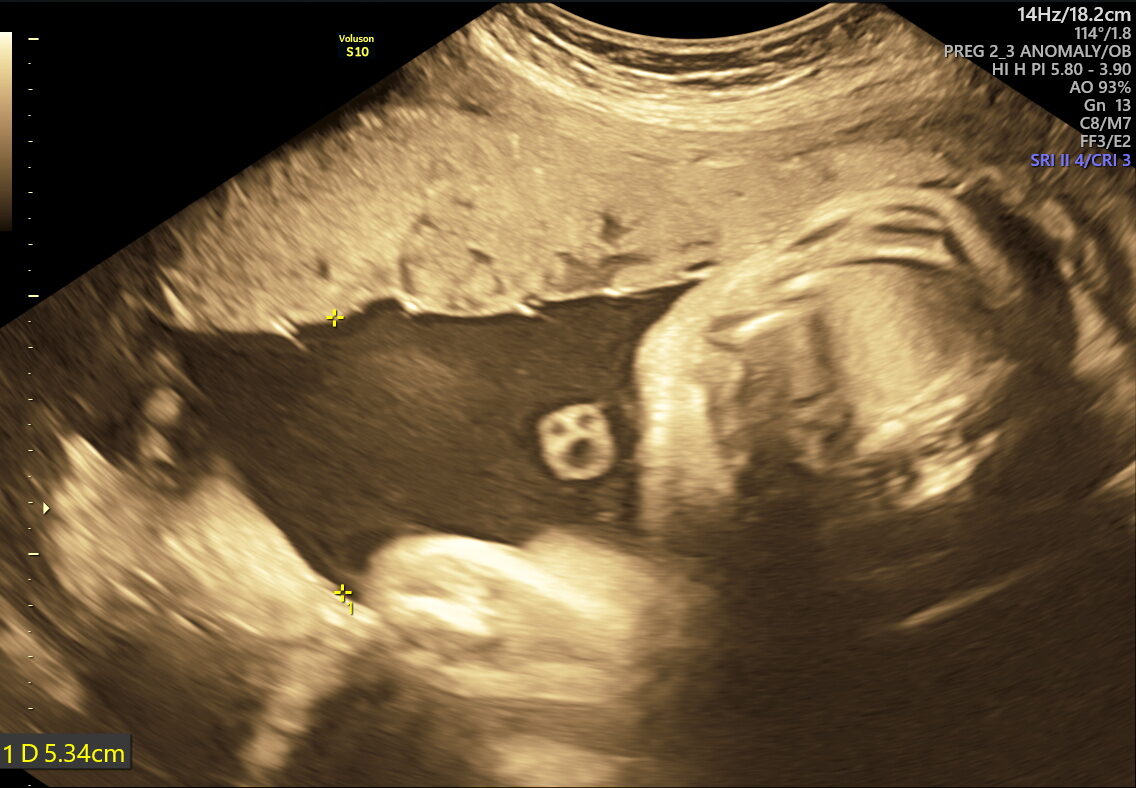

- Fetal Growth & Weight: Verifies if your baby’s size and weight meet healthy expectations for their gestational age.

- Amniotic Fluid Levels: Detects if fluid is too low or high, which could impact delivery and baby’s health.

- Placental Health: Examines if your placenta is supplying nutrients and oxygen effectively.

Common concerns revealed by this scan include:

- Fetal Growth Restriction (FGR) or macrosomia (large baby)

- Abnormal amniotic fluid levels

- Placental aging, detachment, or placenta previa

- Abnormal umbilical cord blood flow or cord entanglement